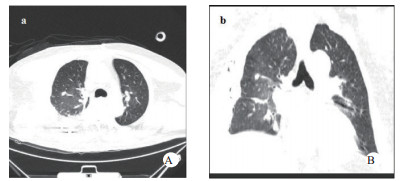

1 资料与方法患者,男,63岁,因“车祸致呼吸困难1 d”入院。既往体健。患者于2019年9月30日翻车致胸部挤压性创伤,伤后出现极度呼吸困难,送至当地医院,测血压80/50 mmHg(1 mmHg=0.133 kPa),胸部CT提示右侧血气胸,给予输血补液、去甲肾上腺素维持血压,经鼻气管插管呼吸机辅助通气,放置胸腔闭式引流管2根。因循环及氧合维持困难,10月1日转至徐州医科大学附属医院,收入EICU。入院查体:T 36.7℃,P 152次/min,R 14次/min(机械通气支持),BP 110/67 mmHg[去甲肾上腺素0.5 μg/kg·min)维持]。处于镇静状态,双侧瞳孔等大等圆,直径约2.0 mm,对光反射未引出;全身多处皮肤软组织擦挫伤,颈部及前胸、上肢广泛皮下气肿,右侧胸壁显著塌陷,反常呼吸,听诊双肺呼吸音低;心率快、心律齐、心音不遥远;腹部无异常体征;2根胸腔闭式引流管引流通畅。入院当天CT检查显示:双侧肋骨骨折伴右侧胸壁塌陷,两肺挫伤、创伤性湿肺,右肺撕裂伤,右侧液气胸,双侧胸壁广泛皮下气肿(图 1:A, B, C);未见颅内出血及腹部器官损伤。入室后0.5 h血气分析:pH 7.18,PCO2 57.5 mmHg,PO2 67.1 mmHg,Lac 4.4 mmol/L,氧合指数67.1 mmHg,APACHE Ⅱ评分27分。治疗上予镇痛镇静、保护性肺通气策略、保温、预防感染等治疗,效果不佳,连枷胸,皮下气肿范围不断扩大,氧合指数持续<100 mmHg。于10月2日气管切开后行V-V ECMO治疗(右股静脉—右颈静脉);因右侧血胸、胸引量24 h达1 000 mL,血红蛋白下降,凝血功能显著异常,存在创伤性凝血病,采取无肝素抗凝ECMO技术,提高血流速(4.6 L / min),气流速(5 L / min),FiO2 100%;给予成分输血,监测ACT及APTT。ECMO转机1h后去甲肾上腺素停用,复查血气分析PO2 105 mmHg。此后,患者氧合和血流动力学逐步改善,创伤性凝血病已纠正,于10月7日在无肝素V-V ECMO支持下行“胸骨骨折切开复位钢板内固定术+右侧3、4、5前肋肋骨骨折环抱器内固定+右侧5、6、7、8后肋肋骨骨折环抱器内固定术+两侧胸腔闭式引流术”。术中见第5肋骨前端骨折向下外移位,3、4肋骨多段骨折,胸壁前上方完全塌陷,肺脏直接外露,胸腔内布满血凝块,术中取出血凝块共约1 000 mL。术后氧分压上升至400 mmHg,术后复查床边胸片,肺部影像学较前改善(图 2 A, B),继续无肝素V-V ECMO治疗1 d后,于10月8日开始肝素抗凝,维持ACT在160 s~180 s,APTT在40 s~50 s,肝素化期间无出血并发症发生。10月11日行自主氧合试验通过,予以撤机。10月12日复查胸部CT两肺复张满意(图 3 A, B),开始间断停用呼吸机并床边康复训练。10月28日撤离呼吸机,气切处高流量吸氧。11月15日拔除气切管。11月18日康复出院,无明显并发症发生。

| 图 2 A入院第一天床边胸片;B术后当天床边胸片。 |

| 图 3 A撤离ECMO第一天胸部CT;B撤离ECMO第一天胸部CT立体成像。 |